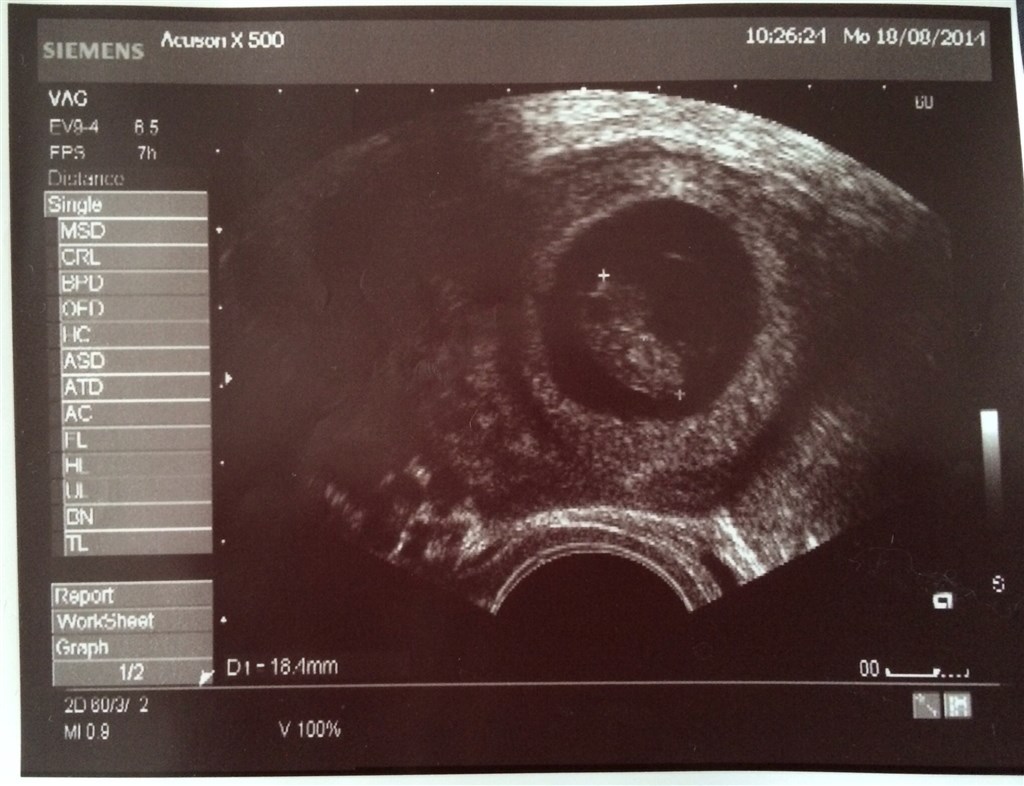

har været til 3 skanninger allerede, de to første var meget tidligt (7+2 & 8+2) , men der var hjerteblink begge gange! Og i dag har vi været til scanning igen er 10+2 og bebs baskede fint med både arme og ben, det var så rørende og livsbekræftende at se!

I får også lige billeder fra scanning i uge 8+2 og 10+2

Vedhæftede fotos (klik for at se i fuld størrelse)